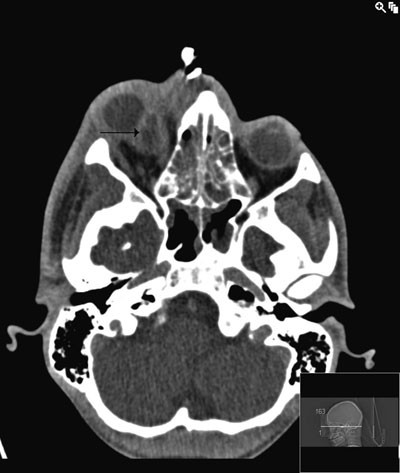

Etter ankomst regionsykehuset ble behandlingen endret etter tilsyn fra infeksjonsmedisiner. Ciprofloksacin 500 mg · 2 intravenøst erstattet gentamycin, da gentamycin har dårlig effekt ved abscesser. I tillegg økte man dosen penicillin fra 2 mill IE til 4 mill IE · 6 og metronidazol fra 500 mg · 2 til 500 mg · 3 intravenøst. CT av bihuler med kontrast viste nå abscess fra pannen og inn i mediale øyevinkel (fig 2). I tillegg så man orbital cellulitt som dislokerte bulbus frem og ned og ga pasienten en kraftig proptose av høyre øye. Det var også en kontrastoppladende oppfylning medialt oppad og baktil for bulbus.